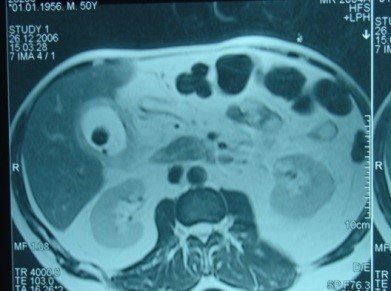

- Zədələnmələrin olub-olmamasını, yеrini və xaraktеrini dəqiqləşdirmək üçün xolangioqrafiya еdilir. MRT ilk seçimdir, lakin dəqiqləşdirmə üçün adətən kontrastlı xolangioqrafiya edilir: əməliyyat vaxtı əməliyyatdaxili xolangioqrafiya, əməliyyatdan sonra isə endoskopik və ya perkutan xolangioqrafiya.

- Öd yollarına yeridilən kontrastın kənara çıxması və ya “blok” (bağlanma) zədələnməni təsdiqləyən əlamətləridir.

Diaqnostik əlamətlər:

- Biliar sızıntı (peritonit, fistul, bilioma, qaraciyərdaxili abseslər) və / və ya mexaniki sarılıq

- Xolangioqrafiyada biliar ekstravazasiya və ya blok